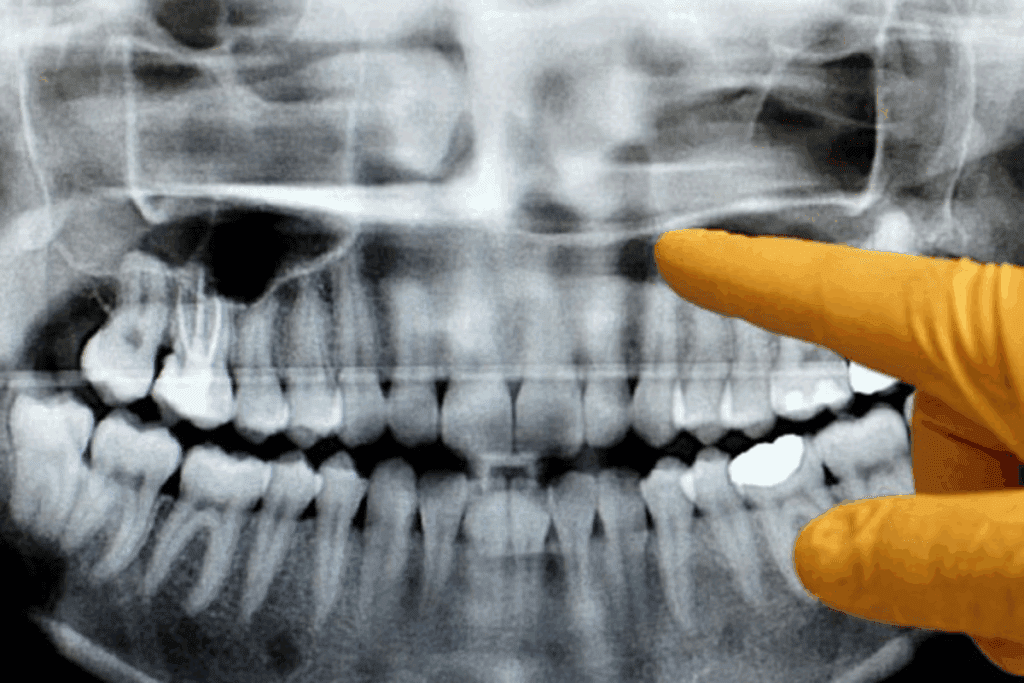

Knowing how to diagnose and screen for oral cancer is key. It helps catch the disease early. Regular dental check-ups are important for spotting oral cancer early.

Professional Oral Cancer Screenings

Professional screenings are a big part of keeping your mouth healthy. A healthcare pro looks for any odd changes in your mouth. This includes unusual patches, lumps, or lesions.

- A thorough visual examination of the lips, tongue, cheeks, gums, and throat.

- A physical examination to feel for lumps or abnormalities.

- A review of the patient’s medical and dental history.

Tests are used to confirm oral cancer. These tests include:

- Biopsy: A procedure where a sample of tissue is taken for examination under a microscope.

- Imaging Tests: Such as CT scans, PET scans, and MRIs, which help determine the stage and spread of the cancer.